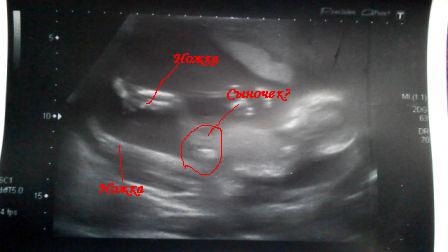

Фото с УЗИ

Пол малышаНЕ особо разбираюсь в УЗИ( До вчерашнего дня вообще не правильно смотрела на это фото. А потом мама моя пояснила так:

По УЗИ сказали мальчик) Правильно ли мама прочитала фото?? И точно ли мальчик? Что то видно по фото??? У кого похожее было??

Моя узистка все так точно показала, аж я со своим -5 увидела. Показала масенькую мошонку и пистолетик. Так что уже без сомнения. А у вас тут в профиль не видно, надо с другого ракурса, сверху и чуть сбоку смотреть.

Я не уверенная, что она именно с этого ракурса его смотрела, но сделала такое фото...

Я вообще вторую ножку не увидела, думала,что они вместе согнуты в коленке)))

я бы тоже сказала, что фото довольно не четкое, тяжело сказать. Но мне фото мальчишеских причандал делали даже крупным планом, но мне все равно было недостаточно понятно))))

Мутное какое то фото. Я только силуэт вижу. А разглядеть пол, думаю это уже у кого какая фантазия)))